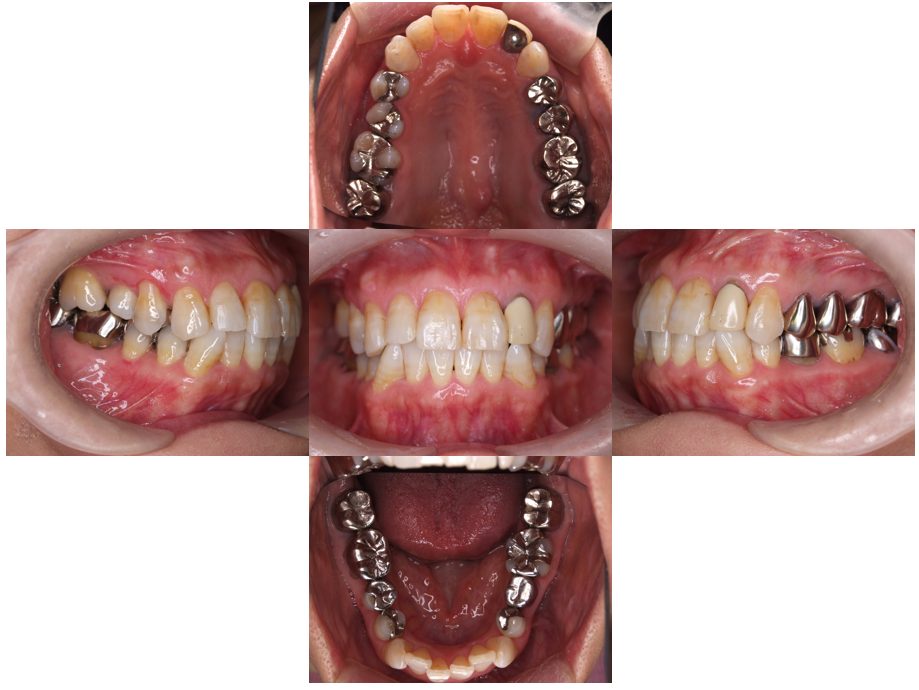

| 主訴 | 50代男性 右上の歯と歯茎が痛い。どこで噛んでいいのか分からないので夜も眠れない |

| 治療内容 | 外科矯正治療・インプラント治療・セラミック治療を行いました。 |

| 治療費 | 4,500,000円(税込み) |

| 治療期間 | 4年(矯正治療期間 3年) |

| 治療回数 | 60回 |

| 想定されたリスク | 顎骨の変形があったので、全身麻酔下による外科処置が必要になり、身体的、精神的負担が増す可能性がありました。 清掃状況によっては矯正中にむし歯が発生するリスクがありました。 |